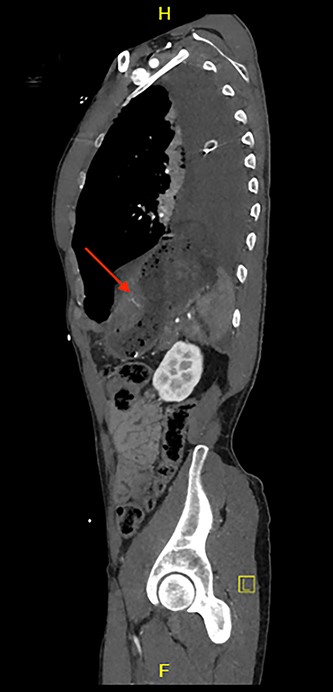

CT scan revealed a large left haemothorax and evidence of left diaphragmatic rupture with herniation of abdominal organs to thoracic cavity such as the spleen, stomach and splenic flexure of the colon; fractured all 12 left ribs, pulmonary contusion, unstable fractures of T6, T10 with acute spinal cord injury (complete transection; Figs 1–3).

Sagittal view of CT scan demonstrates a level of the left hemidiaphragm.